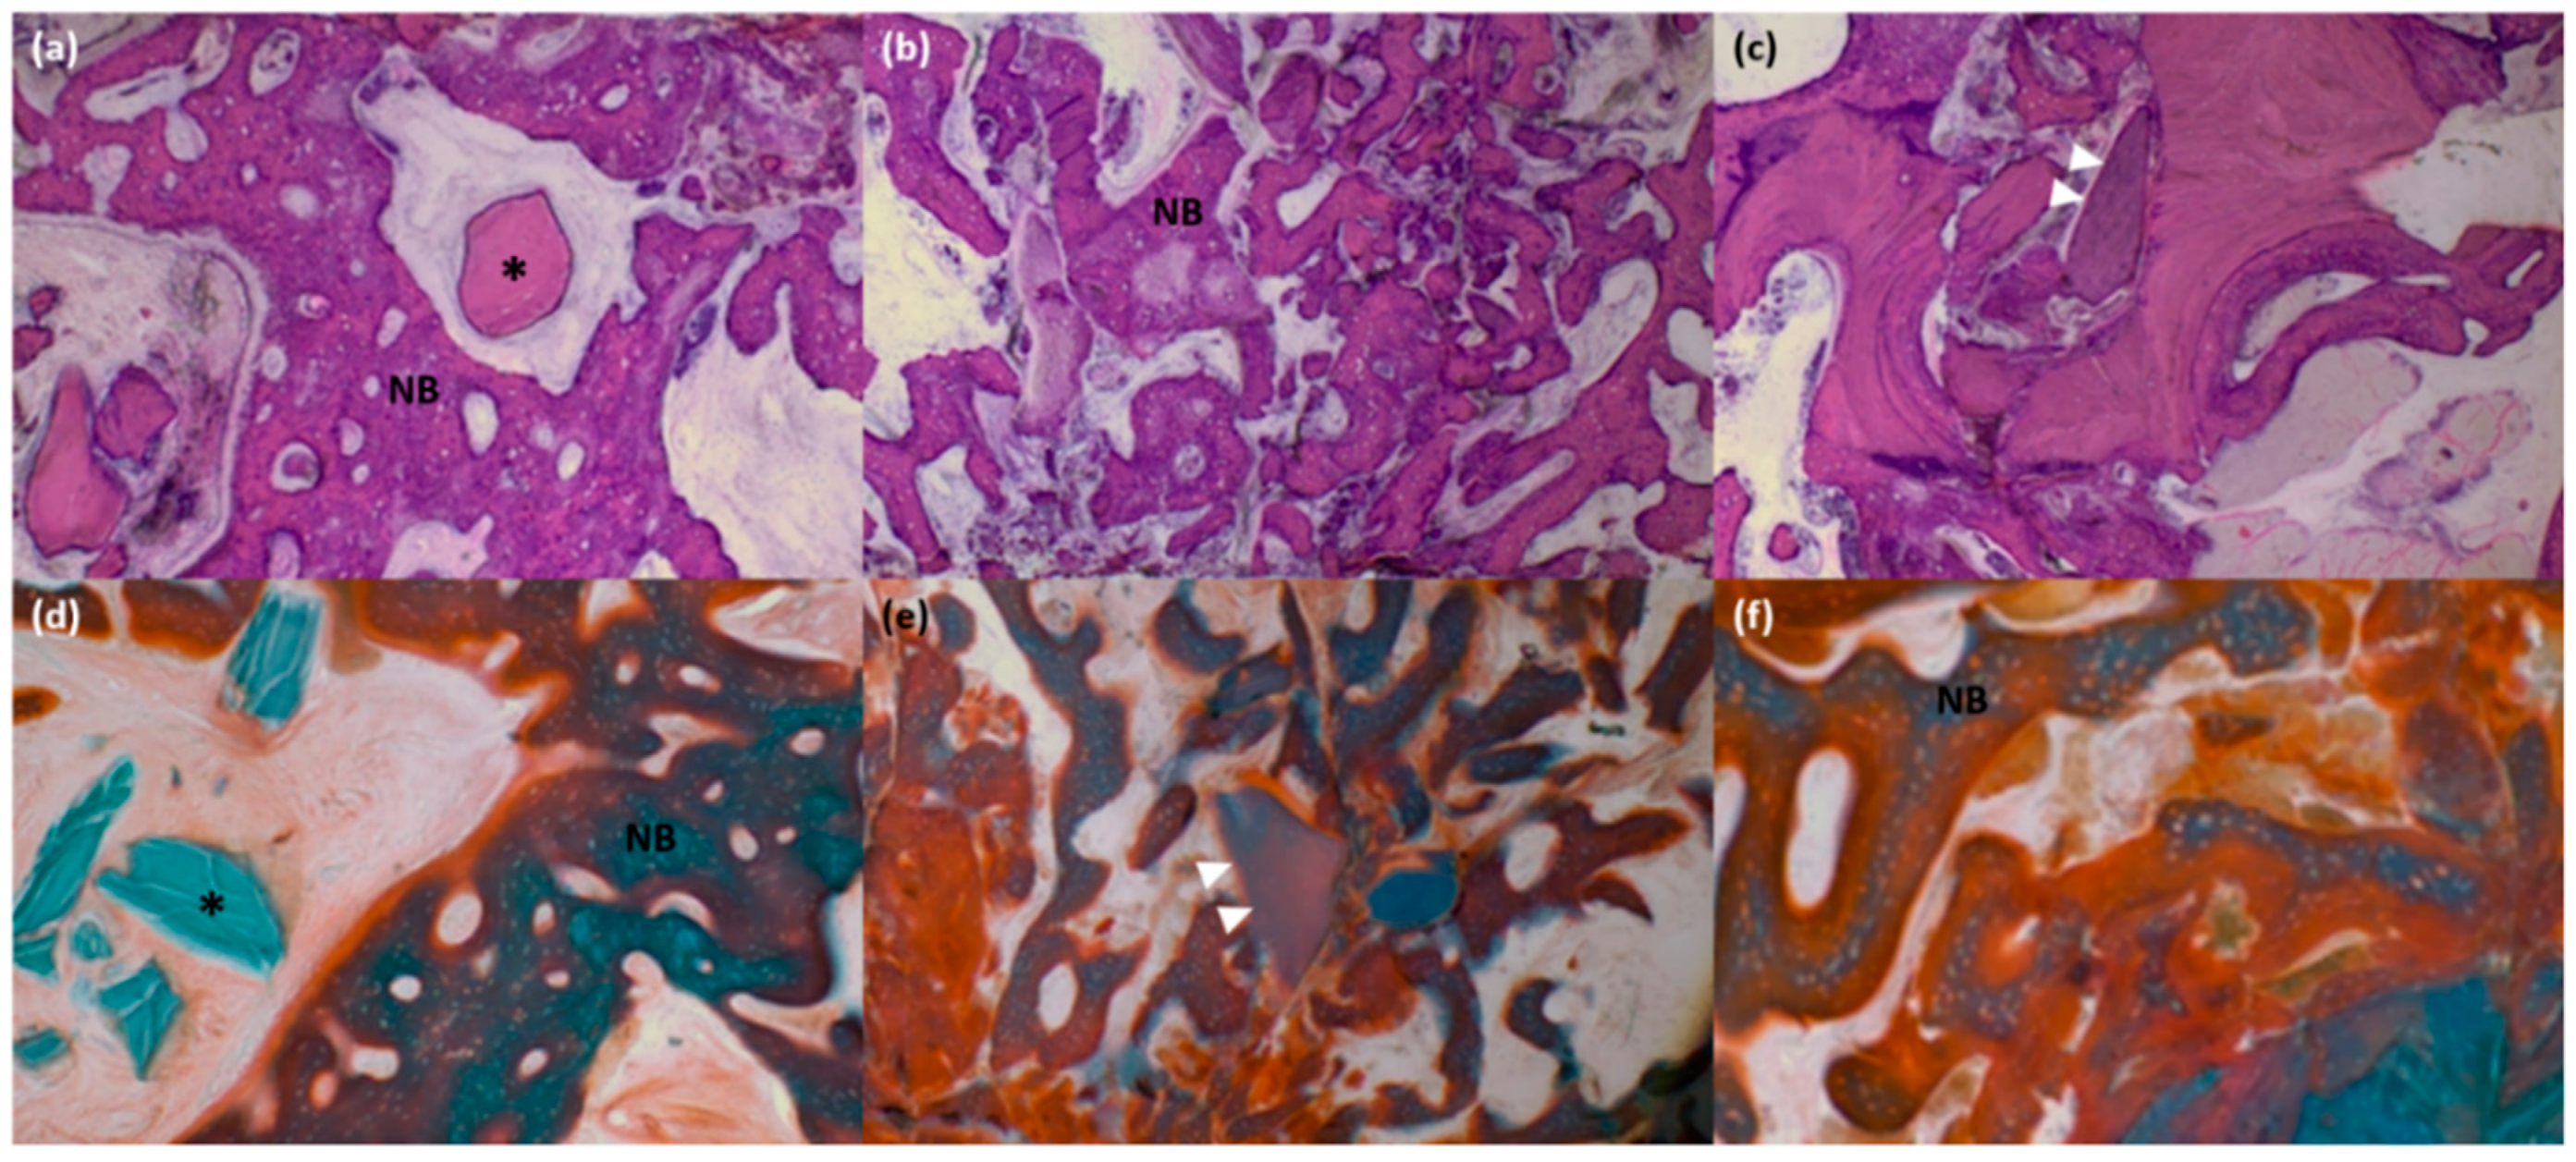

2.8. Histologic and Histomorphometric Evaluation

3.4. Histologic and Histomorphometric Analysis